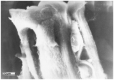

Design: Ten mature New Zealand rabbits were used to obtain 40 condyle specimens. The specimens were passed through ascending grades of alcohol, subjected to critical point drying (CPD), and viewed in the scanning electron microscope. Specimens revealed splits from the dehydration process. When observing the fibers exposed within the opening of the splits, parallel fibers were observed to run in a radial direction, normal to the surface of the articular cartilage, radiating from the deep zone and arcading as they approach the surface layer. After these observations, the same samples were mechanically fractured and damaged by scalpel.

Results: The splits in the articular surface created deep fissures, exposing parallel bundles of collagen fibers, radiating from the deep zone and arcading as they approach the surface layer. On higher magnification, individual fibers were observed to run parallel to one another, traversing radially toward the surface of the articular cartilage and arcading. Mechanical fracturing and scalpel damage induced on the same specimens with the splits showed randomly oriented fibers.